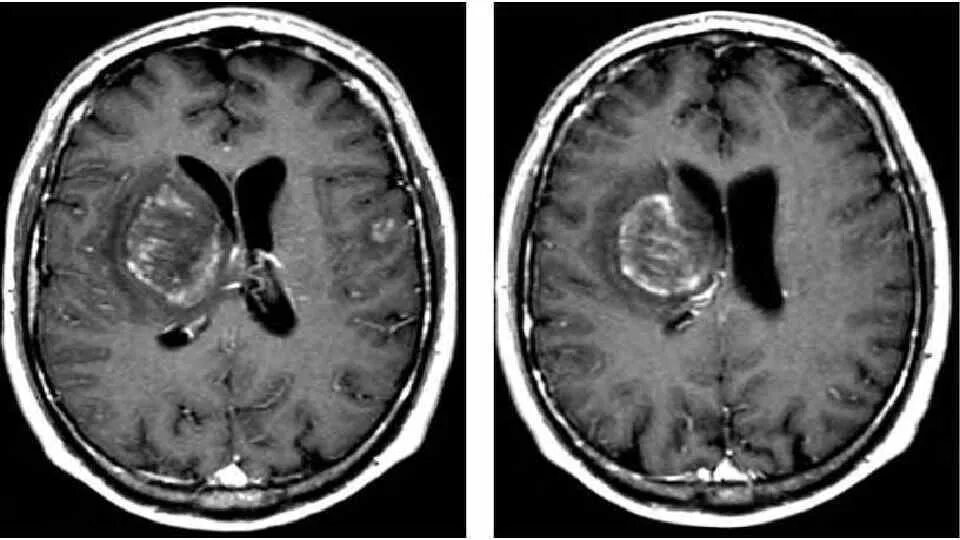

Токсоплазмоз у вич инфицированных